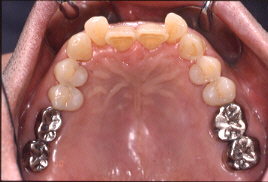

7年経過した状態です(2000年)。